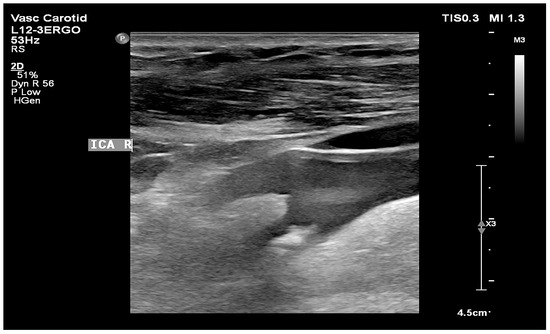

- Atherosclerotic plaque—during the ultrasound examination, the best possible image projection in B-mode presentation was selected with the entire atherosclerotic plaque visible—the image was not enlarged or brightened—according to the accepted standardization. The image of the plaque was recorded on a photograph. Then, to assess the atherosclerotic plaque, images from the ultrasound examination were used to analyze its structure on the GSM scale.

- Images of the visible atherosclerotic plaque in the carotid artery.